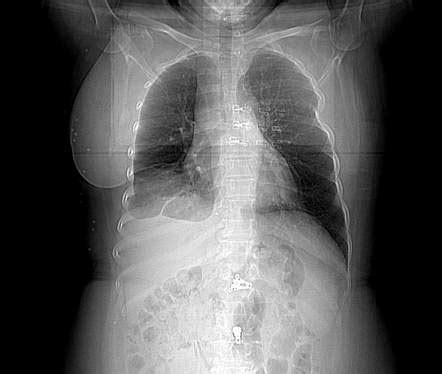

Alright, let’s break down the anatomy of the rib cage. In Malay, the rib cage is known as “ sangkar rusuk .” This bony structure is way more than just a cage; it’s a crucial part of your body’s framework. The rib cage is primarily composed of 12 pairs of ribs. These ribs are curved bones that extend from the spine in your back around to the front of your chest. The first seven pairs are called true ribs because they directly connect to the sternum (or breastbone) through cartilage known as costal cartilage. This direct connection provides stability and support, allowing the rib cage to protect vital organs while still permitting flexibility for breathing.

The next three pairs, ribs eight, nine, and ten, are referred to as false ribs . Unlike the true ribs, they do not directly attach to the sternum. Instead, their costal cartilage connects to the cartilage of the rib above them. This indirect connection provides a degree of flexibility and movement, which is essential for deep breathing and physical activities. The last two pairs, ribs eleven and twelve, are known as floating ribs . These ribs are unique because they only connect to the spine and do not have any connection to the sternum or other ribs in the front of the body. This lack of anterior attachment gives them more mobility, reducing the risk of injury during twisting or bending movements. The spaces between the ribs are filled with intercostal muscles, which play a vital role in breathing. These muscles help expand and contract the rib cage, allowing you to inhale and exhale efficiently. Overall, the rib cage is a marvel of natural engineering, providing a protective yet flexible structure for your chest and abdomen. Understanding the anatomy of the sangkar rusuk can help you appreciate how well-designed our bodies are!